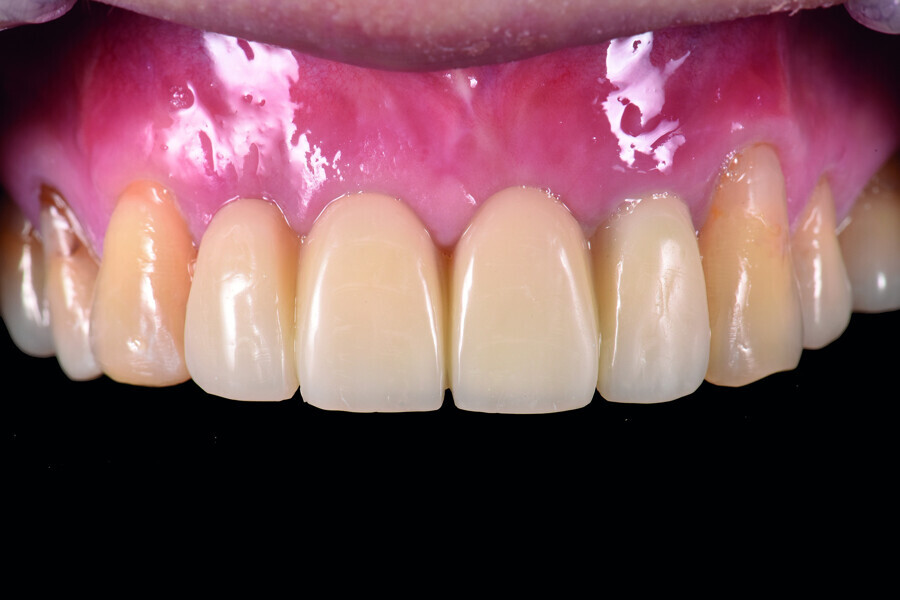

Fig. 1: Pre-op frontal view of the anterior teeth.